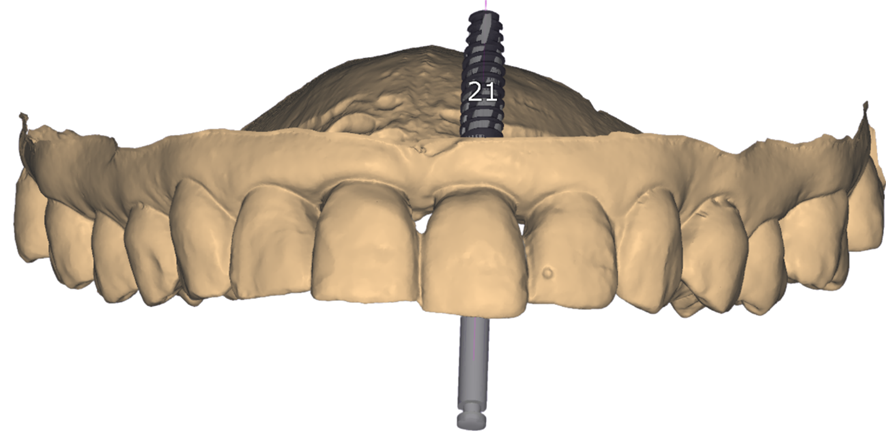

Com auxilio de uma tomografia computadorizada, iniciou-se o planejamento para o implante.

Optou-se por realizar uma cirurgia guiada pela melhor previsibilidade. Foi enviado para a Odontoplanning Brasil® o escaneamento intraoral e os exames tomográficos.

Obtenção de um modelo em 3D para planejamento pela Odontoplanning Brasil®.

Planejamento de melhor posicionamento tridimensional do implante.